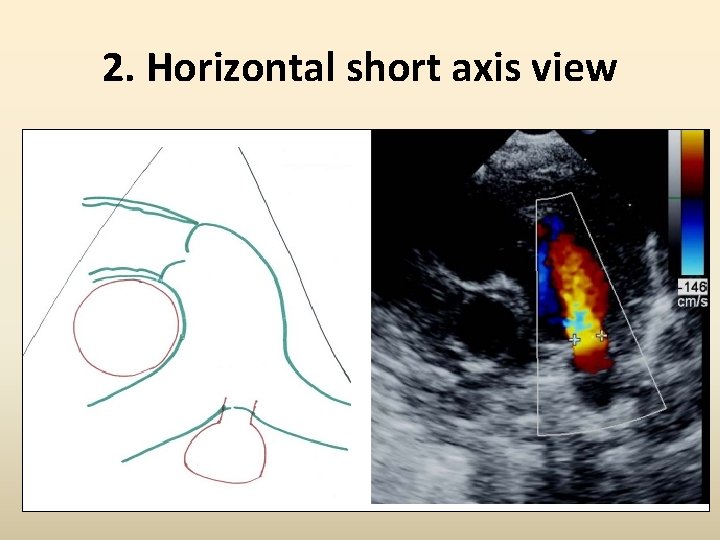

2. Horizontal short axis view